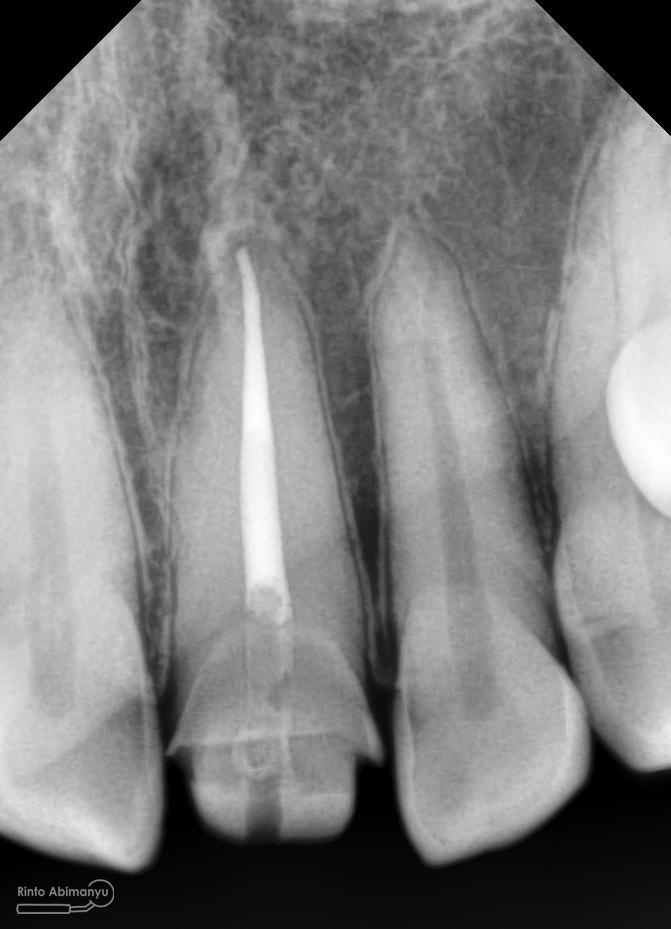

Kemudian dilakukan pengepasan guttap dan difoto ronsen….

Foto radiografis trial guttap

Dari ronsen terlihat guttap sudah pas dan langsung hari itu juga saya lakukan pengisian saluran akar kemudia pasien pulang…. Pada saat selesai pengisian tidak saya lakukan ronsen lagi karena saya merencanakan ronsen evaluasi pengisiannya sekalian foto ronsen saat pengepasan guttap pada gigi 22 saja biar efektif…